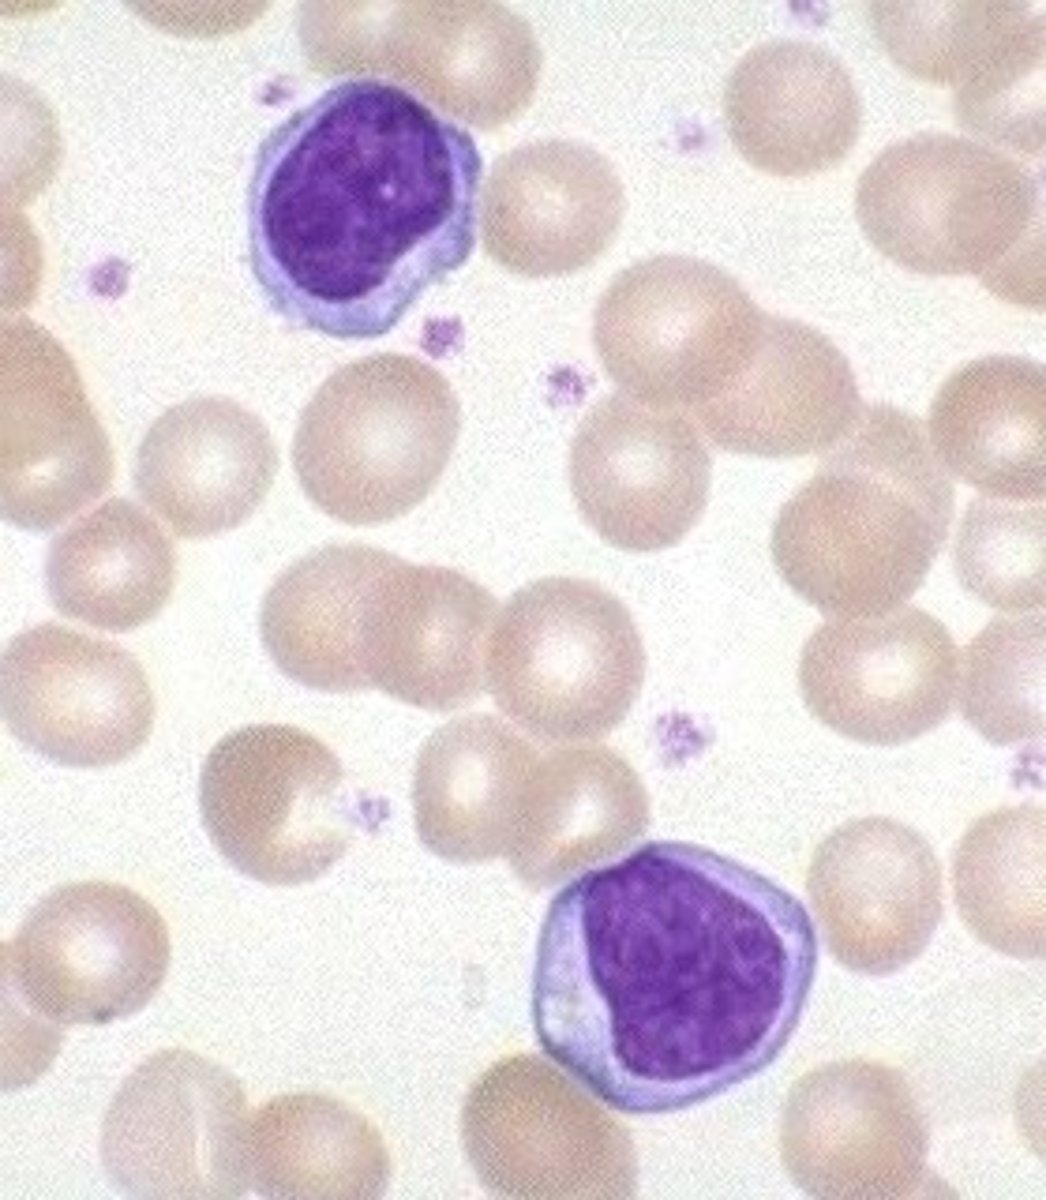

Infectious mononucleosis

Definition: Kissing disease

Etiology: Epstein-Barr virus (EBV)

S+S: Sore throat, fatigue, fever, enlarged spleen, large number of BIG lymphocytes

Treatment: Rest + no exercise

Pathogenesis of mono

EBV enters and multiplies in epithelial cells in mouth --> Spreads to B cells in the throat --> Infected B cells multiply --> Signs and symptoms --> Cytotoxic T cells and NK cells destroy infected B cells --> Recovery